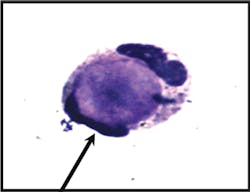

Image 2b

Tart cell: A typical tart cell, which is smaller and has a non-homogenous

(clumped) appearance in contrast to the smooth homogenous character of the

hematoxylin bodies in true LE cells.

cause of the effusion. The phagocytosed debris within the tart cell is

smaller, and has a non-homogenous (clumped) appearance in contrast to the

smooth homogenous character of the hematoxylin bodies in true LE cells (see

Image 2b). LE cells are also seen in bone-marrow aspiration material,